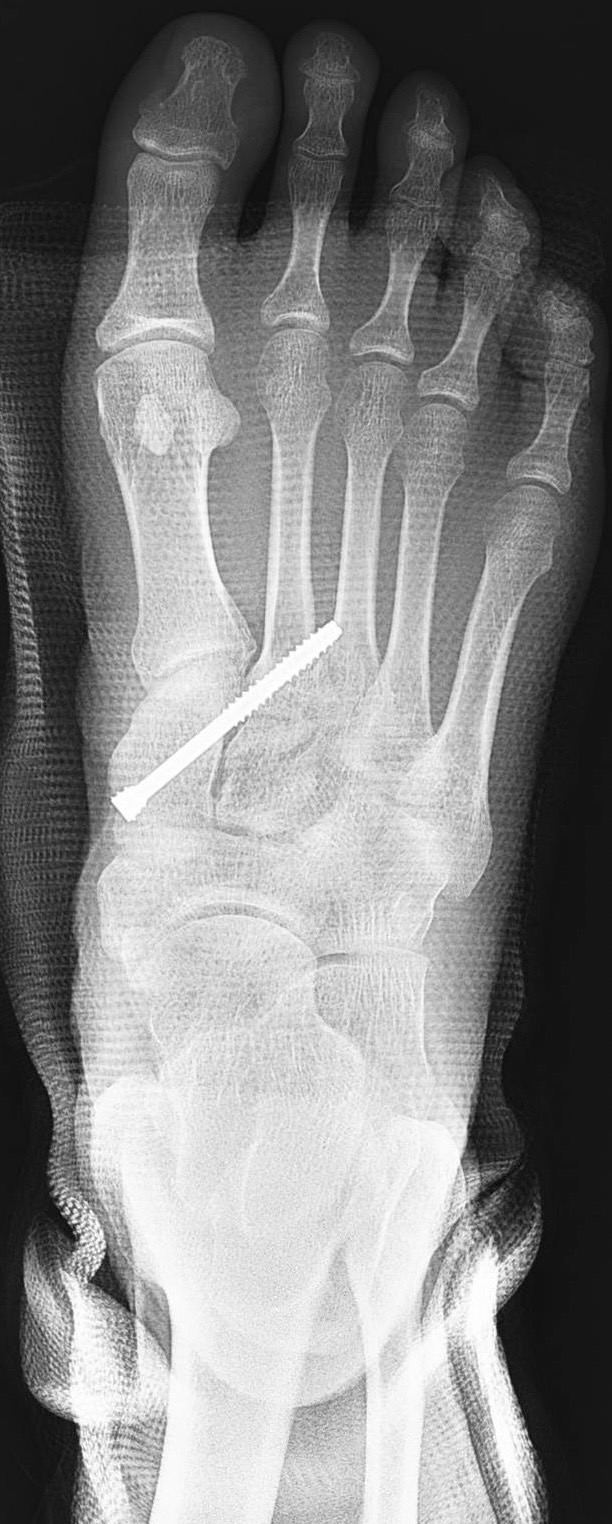

30歲小豪在參加馬拉松比賽時踩空跌倒造成右腳掌疼痛腫脹,腳底也出現瘀血。第一時間至附近醫院的急診室檢查時沒有看到骨折,醫師給了止痛藥並囑咐要抬高冰敷、好好休息。然而,3個禮拜了腳掌依舊瘀青腫脹,一踩就痛。來到大里仁愛醫院骨科的運動醫學特別門診,才發現是腳掌的蹠跗關節韌帶受傷。在劉永川醫師安排微創鋼釘固定手術治療及6週的石膏保護,現在終於回到日常生活,健步如飛。

大里仁愛醫院運動醫學中心劉永川醫師指出,蹠跗關節受傷一般發生在中年男性比較多,會有嚴重的疼痛並且無法負重站立。診斷主要藉由X光或進一步電腦斷層的檢查,核磁共振則可以進一步用在鑑別韌帶的受傷。若是蹠跗關節移位嚴重或合併複雜的骨折需要較大傷口並使用鋼板及骨釘來復位及固定;若是像小豪一樣僅是蹠跗關節韌帶受損則可使用微創骨釘的方式來治療。

劉醫師說,蹠跗關節韌帶受傷不易發現,若沒有儘早處理,會造成足弓塌陷影響行走功能,甚至日後關節退化產生關節炎。輕微的蹠跗關節韌帶使用微創手術治療對軟組織的傷害比較小,恢復效果好。複雜的蹠跗關節韌帶斷裂合併骨折常常有組織嚴重腫脹造成傷口癒合不良的情況,可能需要多次手術重建甚至補皮或皮瓣轉移。民眾可以接受高壓氧治療以促進軟組織消腫,使用富含生長因子的高濃度血小板濃縮液(PRP)注射來幫助修復。